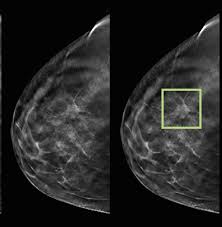

What Does Breast Cancer Look Like On A 3D Mammogram / Mammogram Images Normal And Abnormal - Treatment typically involves some type of surgery and depends upon the staging of the.. The tumor cells don't stay within the clear borders of the mass, but instead invade the nearby breast tissue. The look of breast cancer on a mammogram a tumor or lump will appear as a focused white area on the mammogram. Tumors may be benign or cancerous. Rather than an image that is formed from pictures taken from top to bottom and side to side like a. 3d mammography, or breast tomosynthesis, is a relatively new breast imaging procedure approved by the u.s.

Abnormalities such as cancerous tumors usually appear brighter because they are denser. That makes it easy to detect abnormalities, which generally show up as white. It's so important to listen to the messages our bodies are telling. Ultimately, the news is good: A lump or tumor will show up as a focused white area on a mammogram.

A lump or tumor will show up as a focused white area on a mammogram. It appears to be developing in a concentric pattern. Ultimately, the news is good: These deposits show up as tiny white spots on a mammogram, and there may be only one or two, or too many to count, says jay baker, md, a breast imaging specialist at the duke cancer center.most people assume that what doctors are looking for on a mammogram are lumps, dr. However, when the breast is compressed from top to bottom, the tissue in the upper breast can overlap tissue in the lower breast. What does breast cancer look like on a mammogram? Any area that does not look like normal tissue is a possible cause for concern. Screening mammograms have been used since the 1980s.

The outer edges of these cells look fuzzy or spiky (called spiculated). A false positive is when a mammogram shows an abnormal area that looks like a cancer but turns out to be normal. Most screening mammograms include two views of each breast taken from different angles. A lump or tumor will show up as a focused white area on a mammogram. They will look carefully at the mammogram to interpret the results.